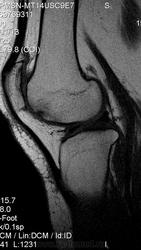

ID:53230

В бедренной кости - Картина последствий остеонекроза. Неоднородный сигнал от собственной связки надколенника ( повышен ) - тендинит ? В подколенной ямке небольшая киста. Как то надколенник высоко расположен. А аксиальные есть еще снимочки ? Травма была ? А еще в надколеннике есть участок отека костного мозга. А сколько лет? И почему пишете наблюдение в динамике? А может имеет место пателло-феморального артроза?

На болезнь Кёнига похоже. Я не большой знаток МРТ, так пока сторонний наблюдатель.

Да, возможно это последствия остеохондрального повреждения мыщелка.

Да, это продолжение темы http://www.radiomed.ru/blogs/helios/mrt-kolennogo-sustavapervye-issledovaniya

Лет- 40. Были небольшие травмочки , за 2 месяца до исследования- эпизод резкого переразгибания.В анамнезе-также ревматизм ( немного сомнительно).

Думаю, что пателло-феморальный артроз имеет место.